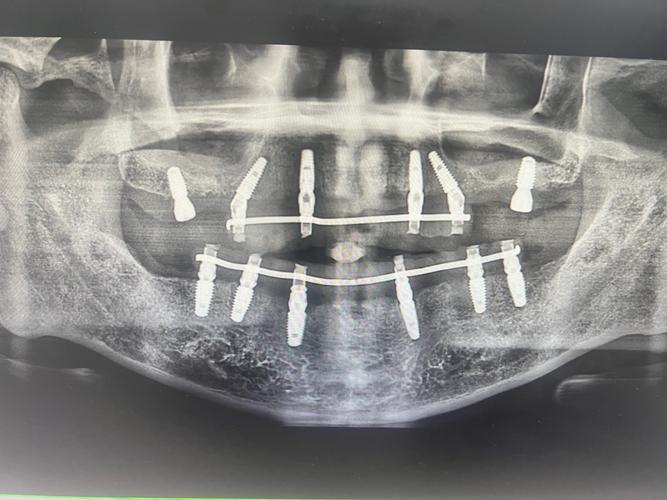

术前评估

- 影像学检查:拍摄CBCT(锥形束CT),精确测量牙槽骨的高度、宽度、密度,评估神经、血管位置;